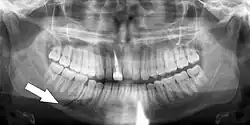

Panoramic radiographs have the capability to demonstrate a portion of the neck and display atheromas (calcifications in the carotid artery) which are an indication of both local and generalized (systemic) atherosclerosis. Atherosclerosis of the coronary arteries leading to myocardial infarction (heart attack), and atherosclerosis of the carotid artery leading to stroke are the number one and number three most common causes of death in the United States.[6]

There is interest to look at panoramic radiographs as a screening tool, however further data is needed with regards if it is able to make a meaningful difference in outcomes.[7]

Additional research projects have further determined the prevalence rate of these atheromas in the general population (3–5%)[8][9] and among high-risk groups (over 25% in: recent stroke victims,[10] individuals with obstructive sleep apnea syndrome,[11][12][13] postmenopausal women,[14] type 2 diabetics,[15][13][16] individuals with dilated cardiomyopathy,[17][13] and among individuals who have received radiotherapy directed at the neck,[18][19]). These findings have been corroborated by other several other researchers.[20][21][22][23][13]

Atherosclerosis is attributed to risk factors that include cigarette smoking, hyperlipidemia, obesity, diabetes mellitus, and hypertension (high blood pressure). These factors, however, do not fully account for the risk of disease. Atherosclerosis has been conceptualized as a chronic inflammatory response to endothelial cell injury[24] and dysfunction possibly arising from chronic dental infection. In 2010, using the previously validated Mattila panoramic radiographic index to quantify the totality of dental infection (i.e., periapical and furcal lesions, pericoronitis sites, carious tooth roots, teeth with pulpal caries, and vertical bony defects), Friedlander's group determined that individuals with carotid artery atheromas on their panoramic radiographs had significantly greater amounts of dental infection/inflammation than atherogenic risk-matched controls devoid of radiographic atheromas.[25][26] While the Mattila index had been previously used to relate the extent of dental infection to coronary artery disease, this research is the first to link the full range of dental disease that it measures to panoramic radiographs evidencing calcified carotid artery atherosclerosis.